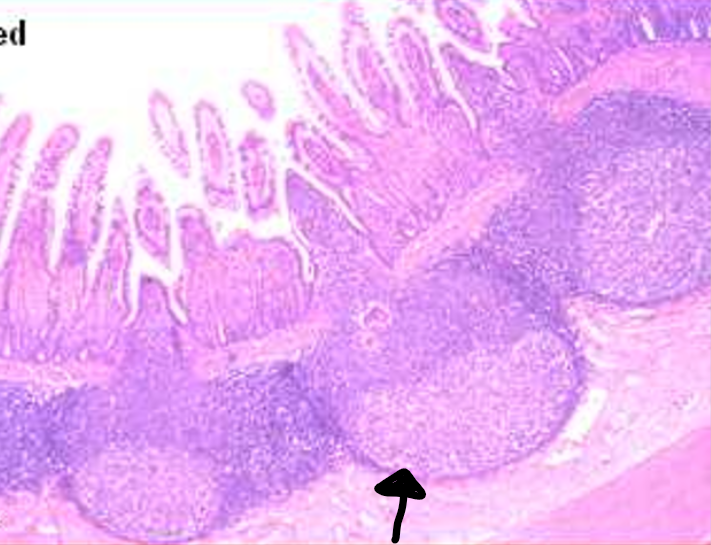

villi

this is from the

ileum

the arrow is pointed to a

Peyer’s patch